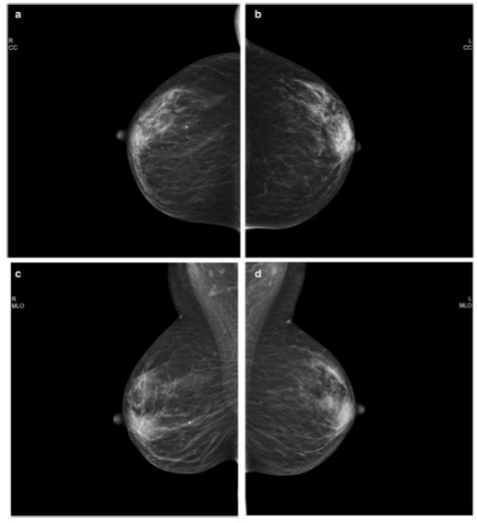

圖 使用PGMI系統歸類為 "完美 "的乳腺鉬靶照片。 a 以病人協助的壓縮模式獲得的右CC視圖。b 以標準壓縮模式獲得的左CC視圖。c 以病人協助的壓縮模式獲得的右MLO視圖

本項前瞻性隨機對照試驗在2017年9月-2019年12月期間進行。參與者是50至69歲的無癥狀女性,每位參與者均參加了第二輪或后續的乳腺鉬靶檢查。通過隨機分配,一個乳腺接受SC檢查,另一個乳腺接受PAC檢查。根據顱底(CC)視圖的10個標準和縱側斜(MLO)視圖的8個標準,圖像質量被評估為完美、良好、中等或不足(PGMI)。進行皮爾遜卡方檢驗,如有必要則進行Yates校正,以比較不同壓縮模式的圖像質量。

共有444名參與者被納入其中(平均[±標準差]年齡,60[±4.9]歲)。在CC視圖中,PAC和SC模式的PGMI百分比沒有差異(完美,37% [162/444] vs 37% [163/444];良好,1% [5/444] vs 2% [9/444];中等,62% [277/444] vs 61% [271/444];不足,0% vs 0. 2% [1/444]; p = .88)或MLO視圖(完美,53% [237/444] vs 56% [247/444]; 良好,22% [99/444] vs 22% [97/444]; 中等,23% [102/444] vs 22% [98/444]; 不夠,1% [6/444] vs 0.5% [2/444]; p = .72)。當按橫向分層或按PGMI標準分析時,也沒有發現統計學差異。